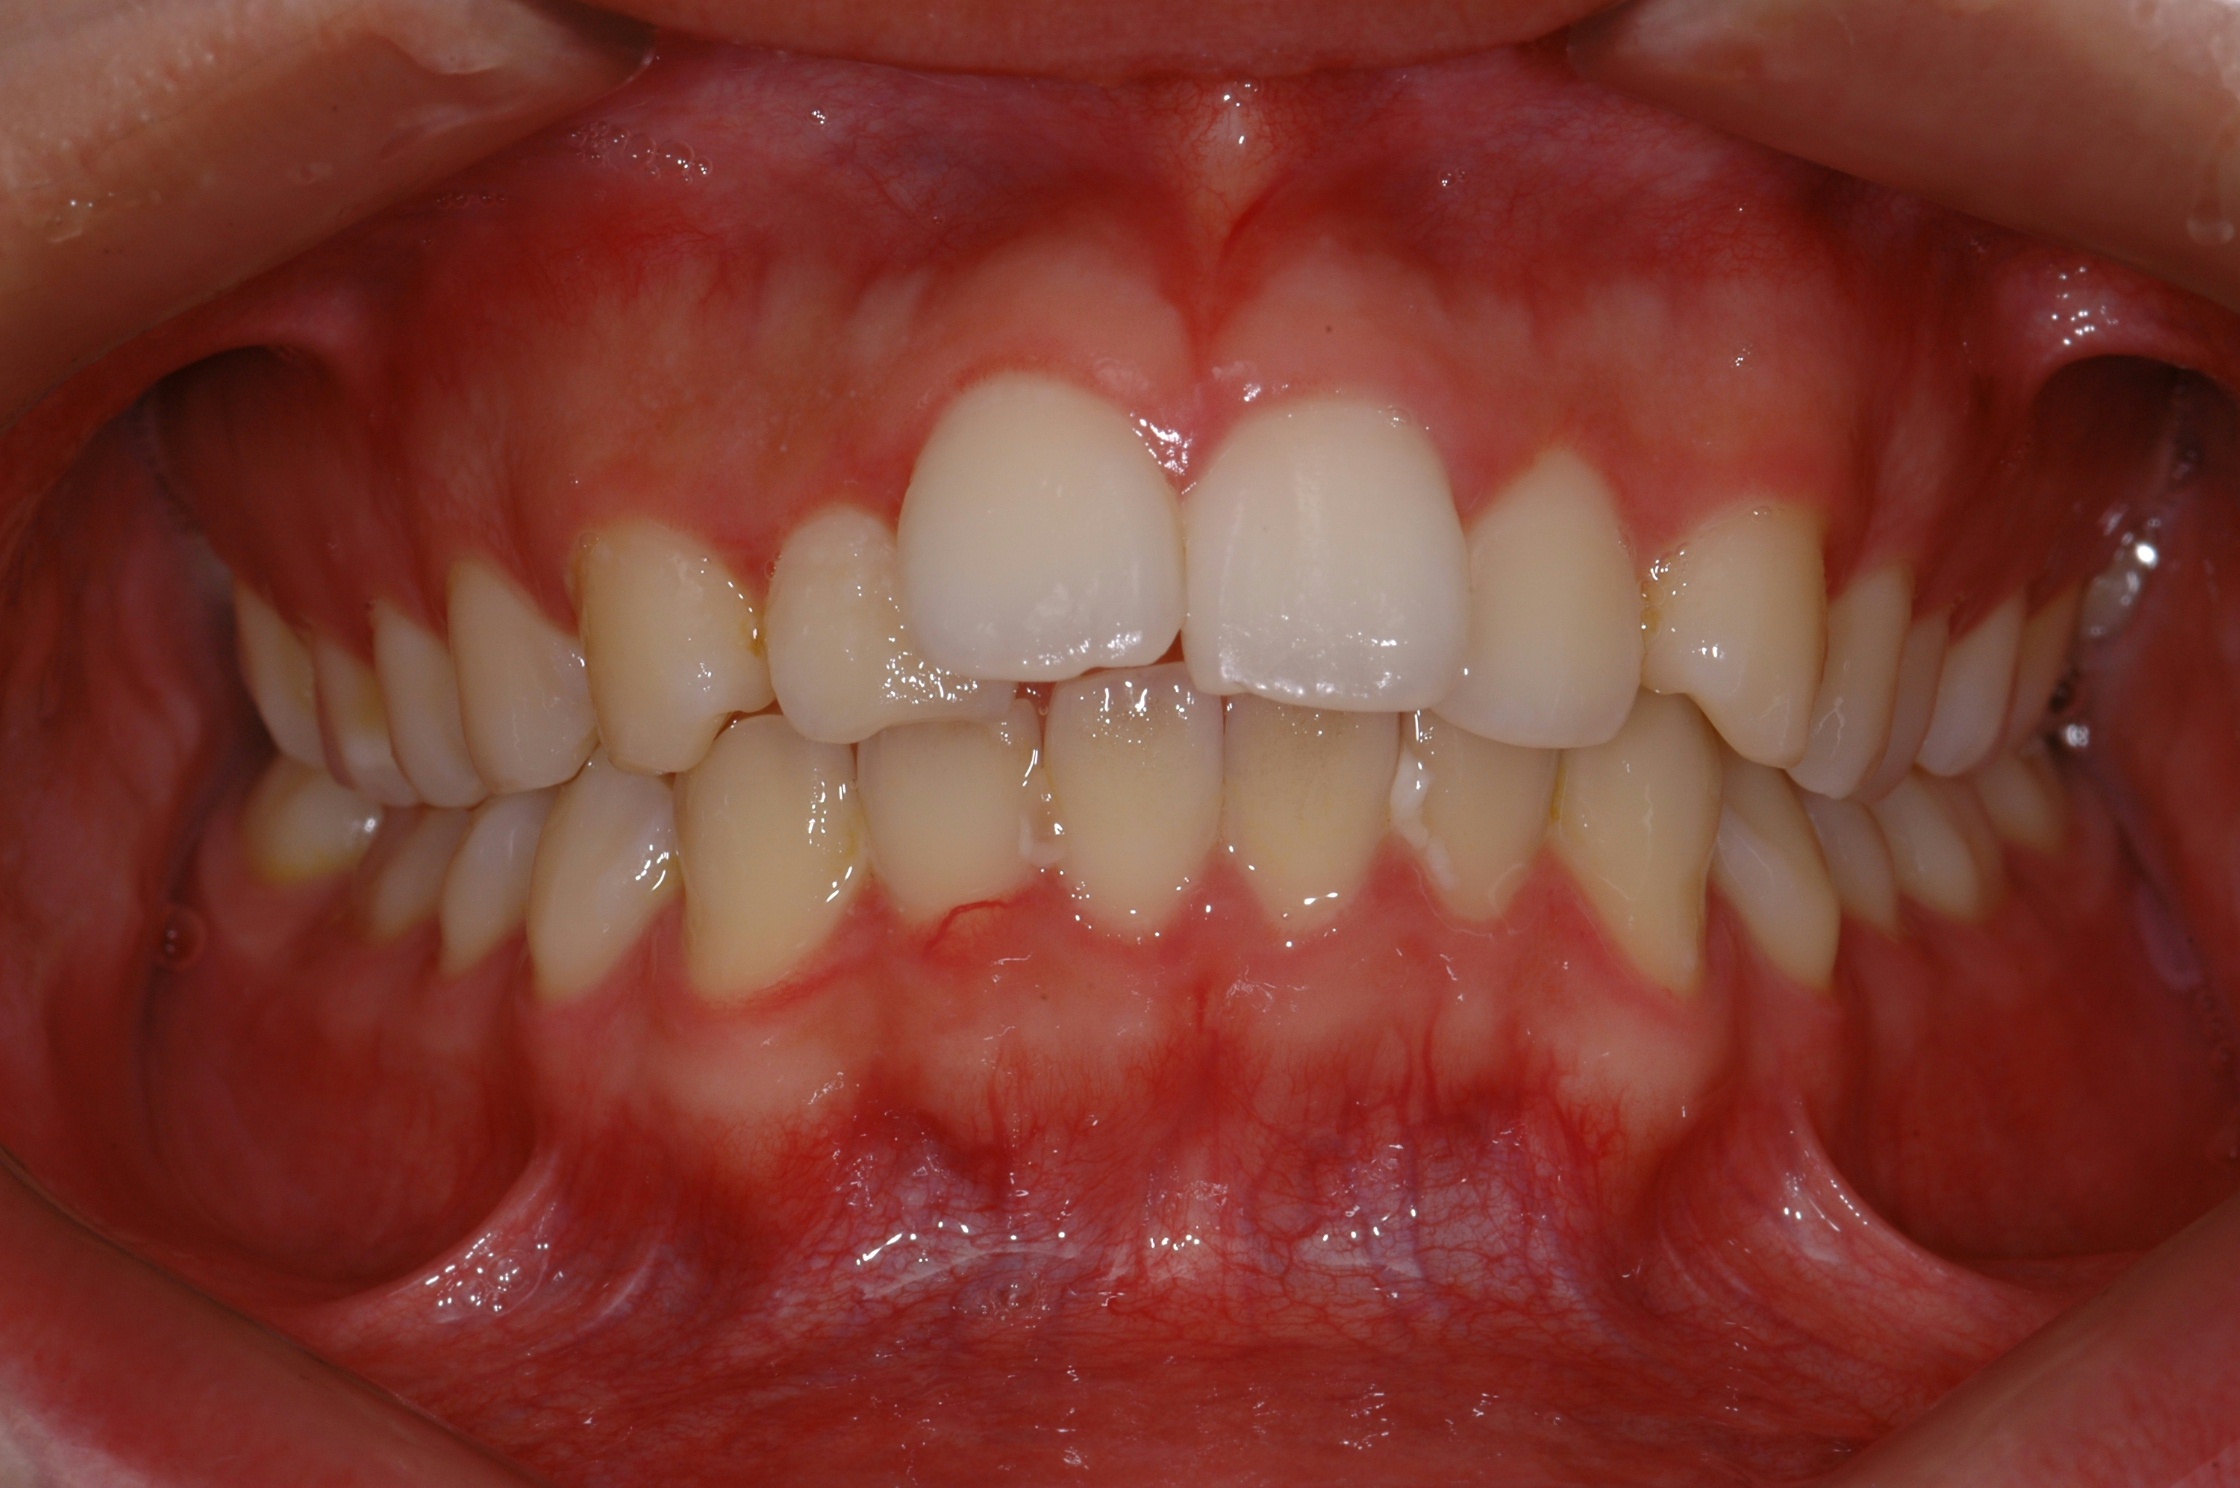

치료 전 사진입니다.